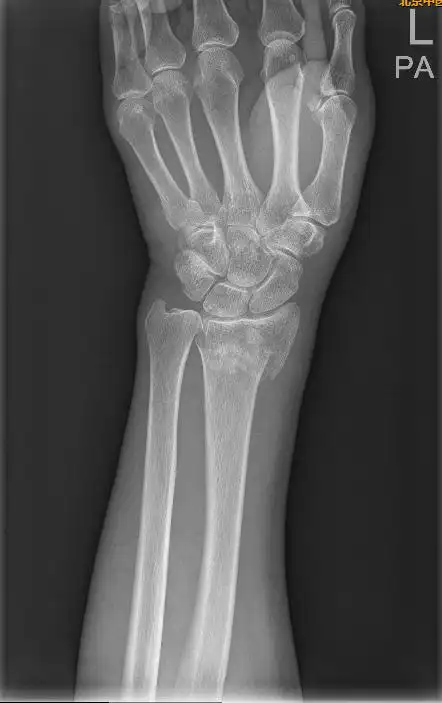

男孩,9岁,左桡骨远端骨折

左桡骨远端骨折